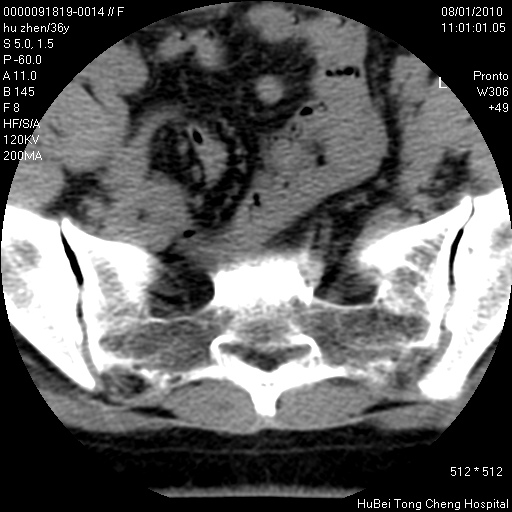

患者 女,36岁。右侧腰腿痛半月余。腰骶椎mr平扫偶然发现骶椎异常信号。

临床诊断:1)腰椎间盘突出症。2)骶椎肿瘤性病变?

骶椎ct平扫(层厚、层距均为5mm),图像如下:

考虑s1骨纤维异常增殖症。